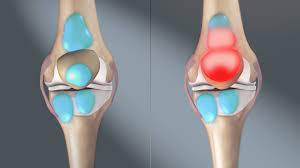

관절염 증상

- 통증: 관절 염증으로 인해 생기는 가장 대표적인 증상입니다. 활동하면서 또는 휴식할 때도 통증이 있을 수 있어요.

- 관절 부어오름: 관절이 부어오르거나 따뜻해지는 증상이 있을 수 있어요.

- 관절 강직: 오랫동안 움직이지 않거나 아침에 일어날 때 관절이 뻣뻣하게 느껴지는 것을 말해요.

- 팽만 및 충혈: 관절 주위의 피부가 붉어지거나 붓는 증상이 있을 수 있어요.

- 움직임 제한: 관절 통증 및 염증으로 인해 움직임이 제한되거나 유연성이 떨어질 수 있어요.

- 딸림 현상: 관절에 뼈가 부딪히거나 문제가 생기면 소리가 나거나 불안한 느낌이 들 수 있어요.